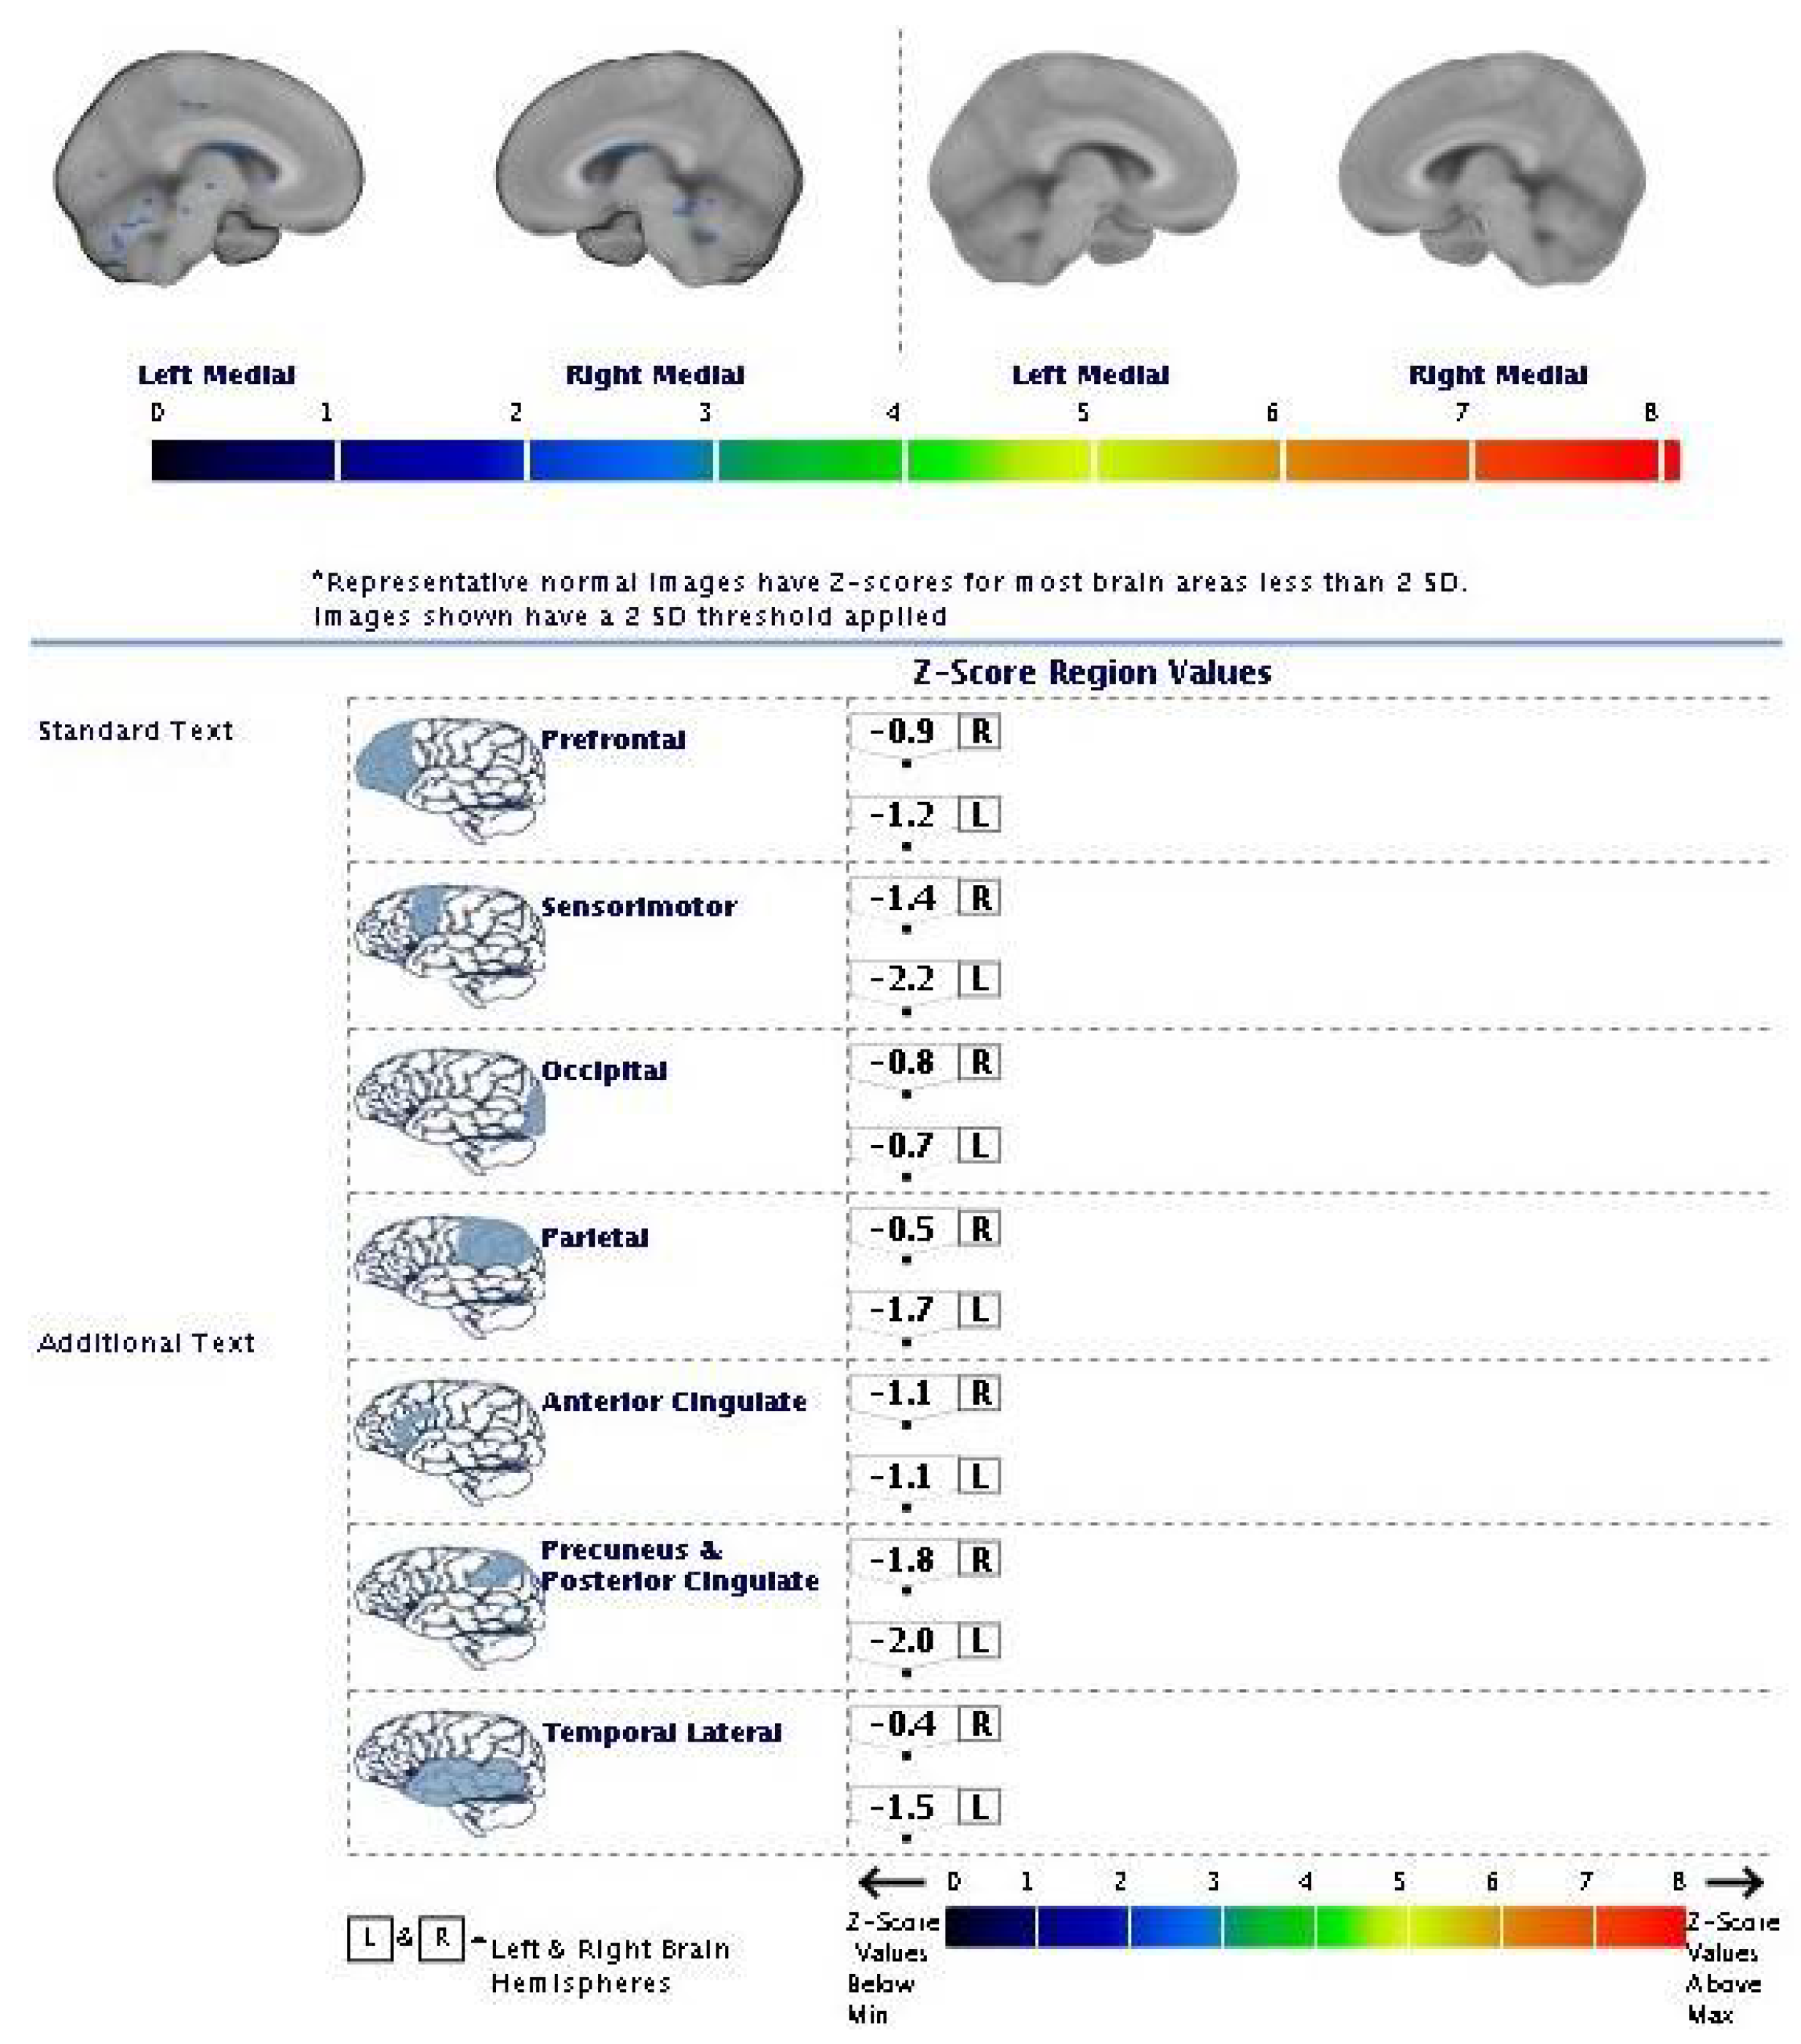

| 2013 | FDG-PET | Hypometabolism in the right and left premotor cortex |

| 2015 | Neurological assessment FDG-PET | Mild isolated motor speech disorder hypometabolism; more extensive involving left temporal gyrus, frontal gyrus bilaterally, cingulate, caudate, and thalamus bilaterally |